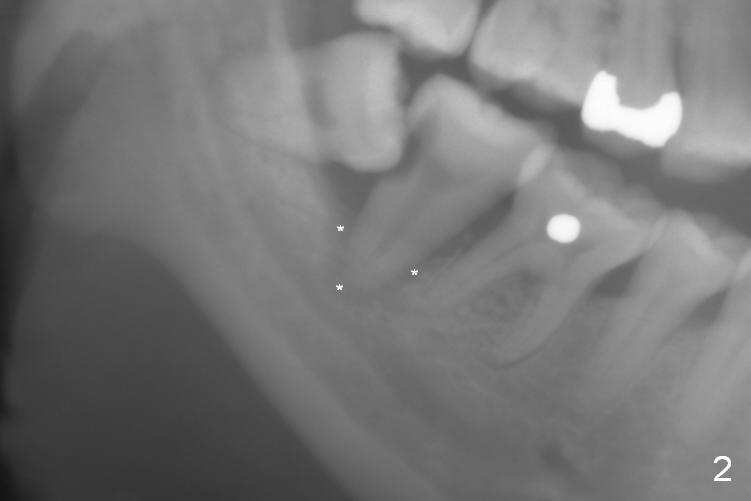

A 39-year-old woman has pain and mobility associated with the tooth #31 (Fig.1 (taken 5 months earlier), 2). It is easy to extract the mesioangularly impacted third molar (#32) after extraction of #31. After debridement and Clindamycin socket disinfection, collagen plug is placed in #32 socket, while allograft in the bottom half of the #31 one. The most coronal portion of the sockets are packed with mixture of collagen and Osteogen plugs and fixed in place with 4-0 Chromic gut (Fig.3). Two or 3 months postop, use #15 to start bone expansion at #31, followed by osteotomes or bone expanders and Tatum tapered taps. Take preop X-ray for depth measurement. The socket is close to the Inferior Alveolar Canal. In one word, no drill will be used for osteotomy. Place bone graft (Fig.4 red circles) prior to implant placement (white outline). Take CT post implant placement to confirm that the Inferior Alveolar Nerve is lingual to the implant.